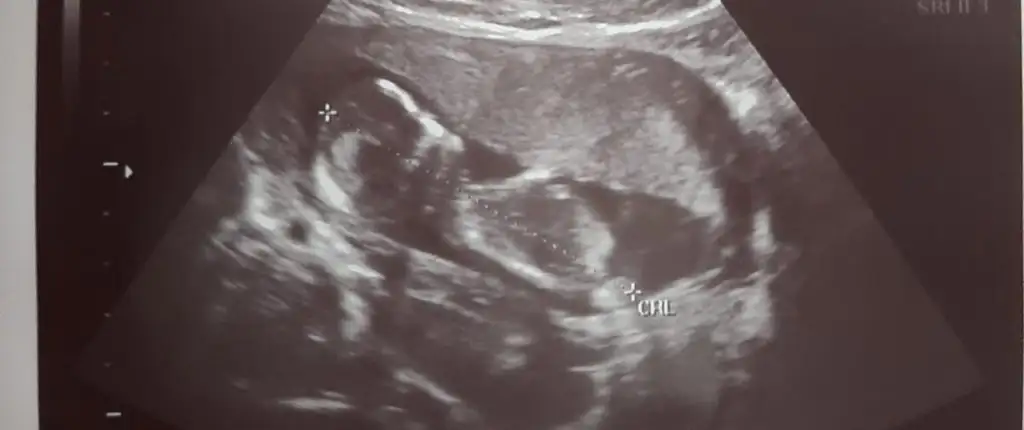

mesajım görünmüyor mu acaba cevap alamadım, 12+5 de 2 li tarama yaptırdım, cinsiyet tahmini yapmadılar, bu görüntüler üzerinden tahmin yapabilirmisiniz

Belkide kızdır çünkü çıkıntı gördüğüm nub ise erkek sanki dedim başka USG varmi

Merhaba daha önce görümcemin bebeginin cinsiyetini bildiniz. Şimdide yiyenin için rica ediyorum bakarmısın lütfen. 12 hafta karından. Ikra meyra Ikra meyra